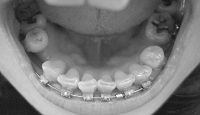

下のワイヤーは一番太いものになったので、今回の調整でキレイなアーチ状に揃ってくれるはず

順調なら、次回から抜歯痕を詰める作業にはいりますっ